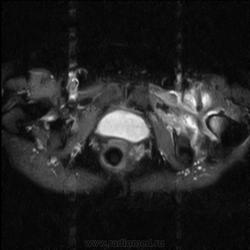

МРТ тазобедренный сустав (срочно)

Пациентка 1944г. р. Жалобы на боль области сустава в течении месяца. Температуры не отмечала. Серьезных травм со слов не было. Внешний осмотр новых данных не дал.

Дайкомы пока не смотрела-скорость интернета дома небольшая.Думаю, что здесь проблемы в суставе и параартикулярных мягких тканях.Не так давно у меня что-то похожее было.

типа бурсита тазобедренного сустава? подвздошно-гребешковая сумка получается

А как вам стенка прямой кишки?

Да, еще подвздошная область.

Подозрительная, но неубедительно пока.Ни одного сагитталла не вижу с прямой кишкой.Нужно дообследовать однозначно.